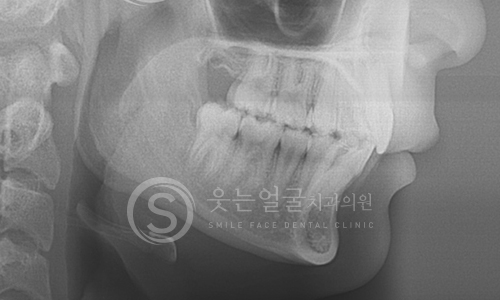

웃는얼굴치과의 12단계 교정진단시스템은 환자의 치아와 턱 구조,

얼굴 균형, 교합 상태 등을 체계적으로 분석하여

최적의 치료 계획을 수립하는 첨단 진단 프로세스입니다.

02 파노라마 촬영

03 세팔로 촬영

04 턱관절 검사

05 정면 X-ray 촬영